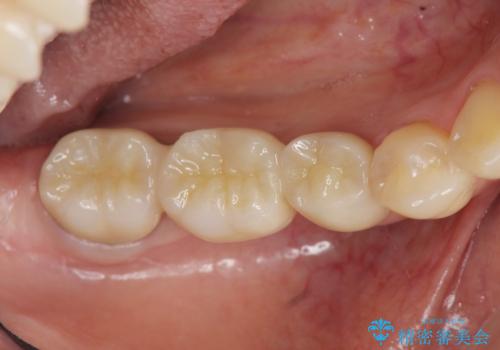

ブリッジ治療で比較的早期に咬合機能を回復することができました。